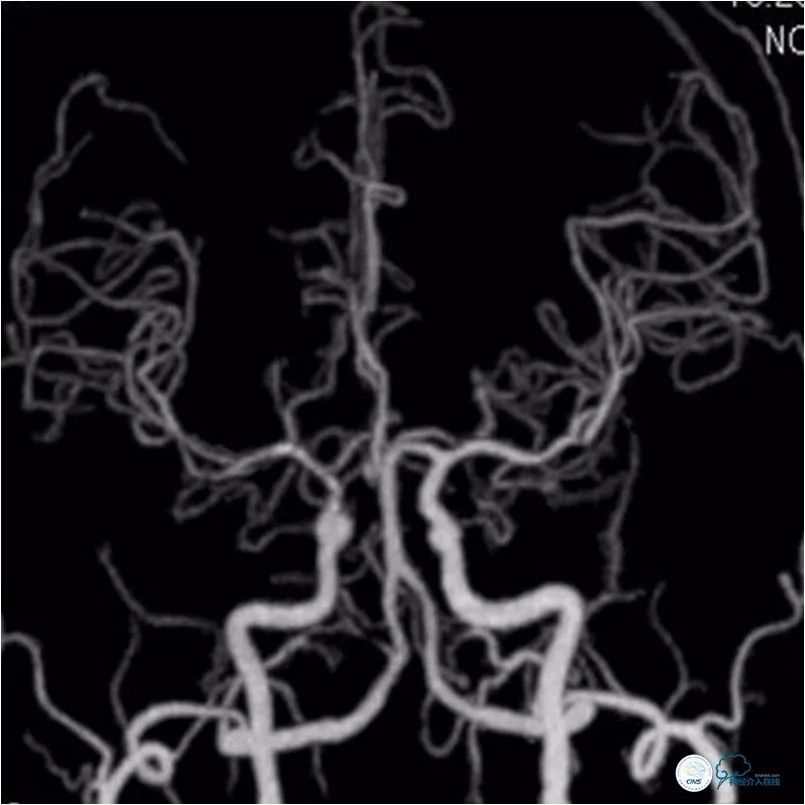

术后复查头颅CTA:右颈内动脉C7段支架通畅(图10)。

图10

CTP:未见明显灌注异常(图11)。

图11